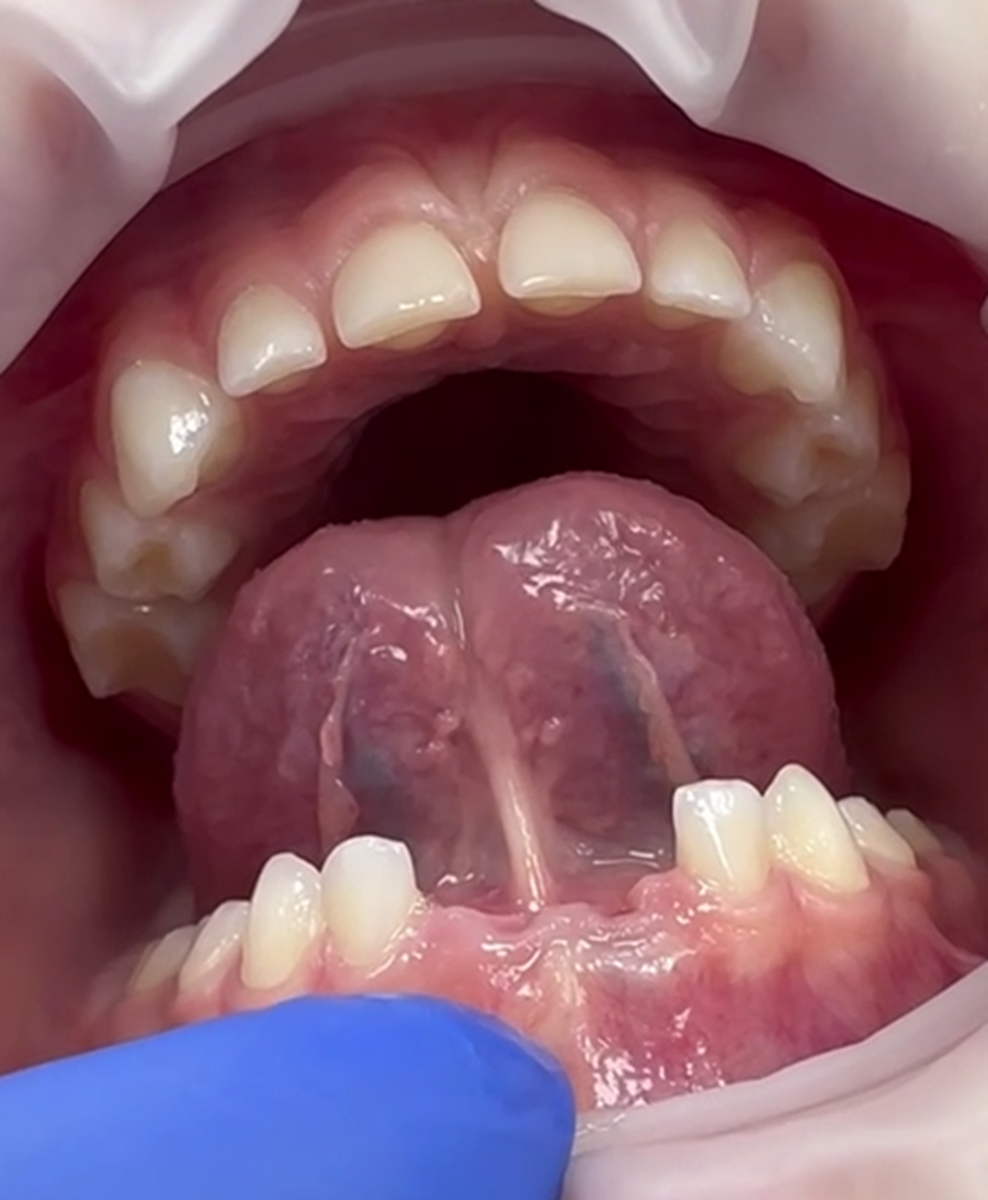

Клинический случай: коррекция уздечки языка

Малышка Мария 4,5 лет попала к нам в клинику по рекомендации логопеда, который постоянно направляет к нам на коррекцию уздечки языка.

При осмотре было выявлено ограничение движения языка.

Уздечка языка одним своим концом вплетается в подъязычное пространство, другим в верхней трети языка.

Длина уздечки — основной характеризующий ее параметр, и от этого будет многое зависеть.

В норме уздечка должна прикрепляться к нижней трети языка, если же она вплетается выше, то диагноз — короткая уздечка языка или анкилоглоссия.

Абсолютным показанием к коррекции уздечки ее прикрепление в верхней трети языка. Что и было у Марии.